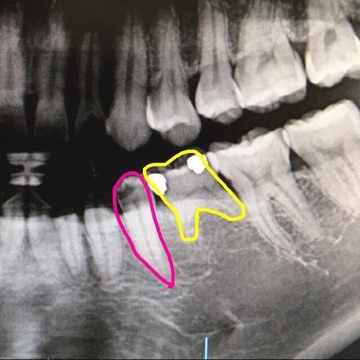

衝撃写真かも。。。

そんでぼくには乳歯がまだある

本来なら、ピンクのサイズの

大人の歯が生えてくるはずだったのに

大人の歯が存在しなかったの。

だからそのまま乳歯が残ってるんだって〜

詰め物してなんとか持ちこたえてる。